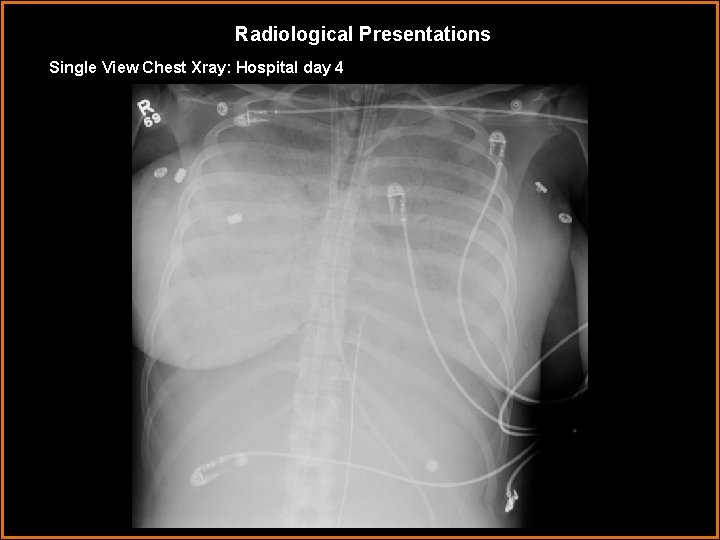

Radiological Presentations Single View Chest Xray: Hospital day 4

Findings and Differentials Findings: Hospital Day 1: Bilateral airspace opacification with lower lobe predominance and air bronchograms. Endotracheal intubation, right internal jugular central venous catheter. Hospital Day 4: Interval progression diffuse opacification of the lungs bilaterally with air bronchograms. ET, nasogastric tubes in appropriate positioning. Left internal jugular central venous catheter terminating in the left subclavian vein. Right internal jugular catheter and IVC catheter. Differentials: • Cocaine-related acute respiratory failure with right venous stent for iatrogenic injury to jugular vein • Peripartum Cardiomyopathy and bilateral internal jugular venous access • Sepsis secondary to intrauterine fetal demise with femoral catheter • ARDS with ECMO support